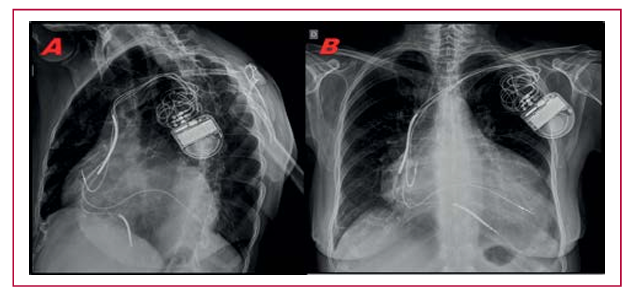

Introducción: La terapia de resincronización cardíaca presenta una tasa de un 25%-30% de pacientes “no respondedores”. La resincronización endocárdica, en la que el catéter del ventrículo izquierdo se implanta en el endocardio, sería una alternativa para estos pacientes, aunque su evolución a largo plazo no ha sido investigada.

Métodos: Se incluyeron pacientes implantados según los criterios para resincronización, usando la técnica Jurdham, con más de 6 meses desde el implante. Todos eran respondedores clínicos.